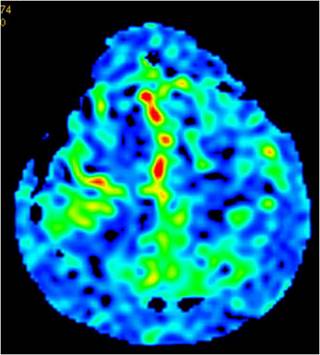

入院后,患者完善了所有检查;TCD提示:左侧大脑中动脉中度狭窄;右侧大脑中动脉血流减慢;左侧大脑前动脉及大脑后动脉血流速度增快;右侧大脑后动脉血流速度减慢。颅脑MRI-ASL提示:左侧额顶叶灌注低(如图2)。DSA影像显示:烟雾病(如图3)双侧颈内动脉末端闭塞,颅底可见烟雾状血管生成部分代偿供血。

图2,额顶区低灌注